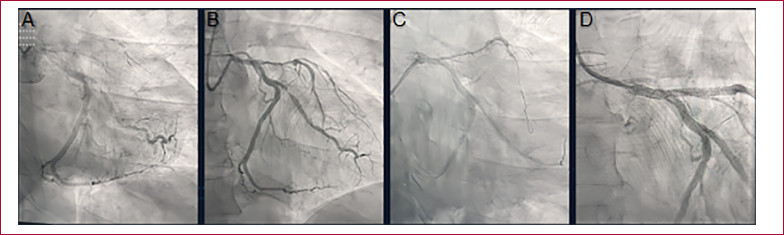

Fig. 2

Coronary angiography (CAG). A. CAG on admission. B. CAG 24 h after treatment with fibrinolytics. C. PCI of the culprit lesion, guidewire in the left anterior descending artery. D. Final angiographic result after stent placement.

He was admitted at 10 p.m. with persistent precordial pain and an ECG showing the previously described changes (Figure 1). Coronary angiography was performed via left radial artery access, with a door-to-needle time of 10 minutes (Figure 2 A). It revealed occlusion of the left anterior descending (LAD) artery at its origin, and faint opacification of the distal bed through homocoronary and heterocoronary collateral circulation. The lateroventricular branch of the circumflex artery showed an 80% stenosis in the proximal third. The right coronary artery was occluded in the middle third, and its distal bed was opacified through homocoronary collateral circulation.

Twenty-four hours after admission, a new coronary angiography showed an ulcerated lesion in the left main coronary artery and a patent left anterior descending artery, with an extensive severe lesion from its origin to the middle third, showing TIMI II flow (Figure 2 B). The rest of the arteries showed no changes compared to the previous catheterization. During this procedure, PCI was performed on the left anterior descending artery with placement of two drug-eluting stents, on the left main coronary artery with one drug-eluting stent, and on the circumflex artery with two drug-eluting stents.

The procedure was performed via radial access without complications (Figure 2 C and D).